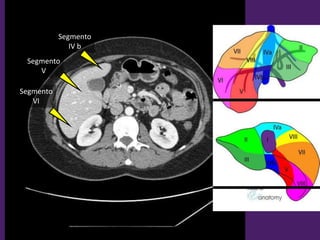

Bonus track:

Segmentación

del hígado

Vista Anterior. Vista Posterior.

Segmentación hepática

Vista superior Vista inferior

Segmento

II

III

IV a

VIII

VII

IV

I

Receso de

Rex

IV b

V

VI

L1-L2

L2